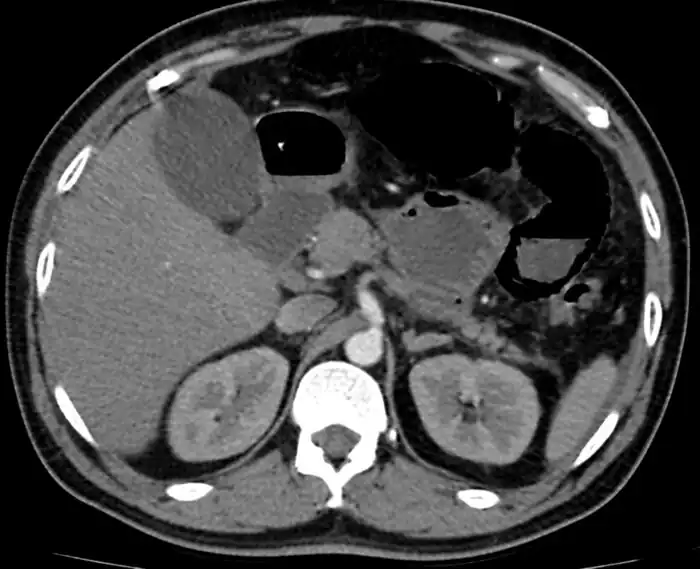

Mesenteric ischemia/CT image

Mesenteric ischemia